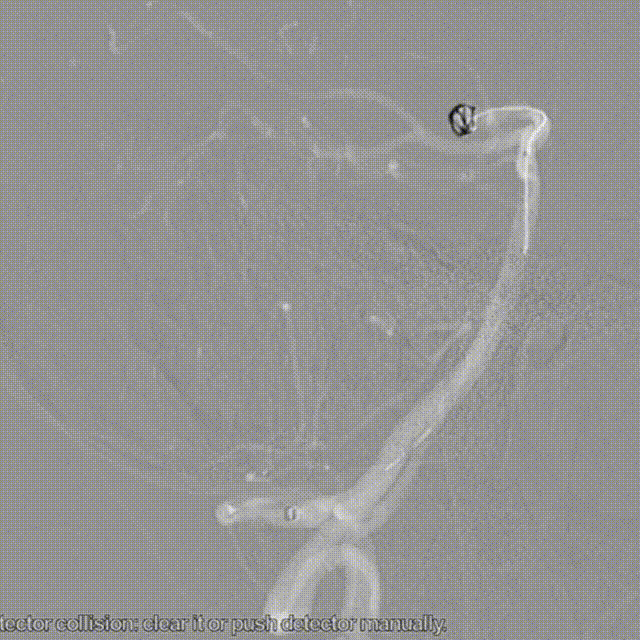

支架微导管到达P1。

支架微导管在Synchro微导丝引导下顺滑到达P2以远。

微导管冒烟检查远端血管情况。

Echlon-10进入P1。

Echlon-10在Synchro引导下进入瘤腔。

2.5*20强易达密网支架定位。

回撤支架导管原位释放支架,头端打开并锚定。

检查造影,透视下观察支架头端打开与贴壁状态。

支架中段遇到弯折处打开不良,先整体推挤支架和微导管蓄积张力,后回撤微导管撤掉部分张力,基本保持等张释放,支架中段打开良好。

透射下多角度检查支架打开和贴壁情况,观察到支架中段打开良好。

回撤微导管完全释放支架。

造影检查支架近端打开情况,此时观察到明显造影剂滞留现象。